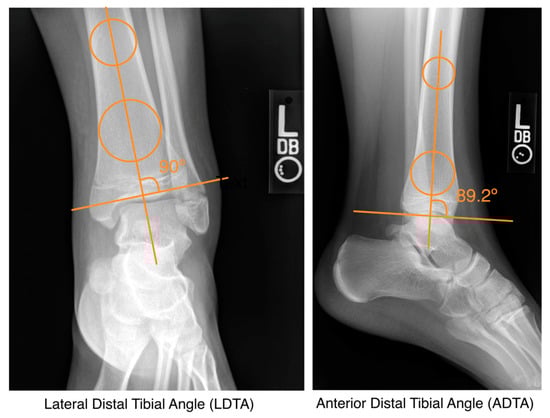

We recorded demographic and clinical factors such as age, sex, race, activity associated with injury, length of follow-up, and management. We performed radiographic reviews of the post-reduction AP, mortise, and lateral X-rays and recorded displacement, anterior distal tibial angle (ADTA), and lateral distal tibial angle (LDTA) (Figure 1). For surgical patients, measurements were taken after closed reduction in the emergency room but before surgical reduction. These parameters were selected to assess the displacement and angulation of the fracture. All radiographs were independently measured by two different reviewers and confirmed by calculating interclass correlation coefficients (ICCs). Any major discrepancies were resolved by a third reviewer. To assess outcomes such as PPC, we identified patients with ≥6 month of radiographic follow-up and evaluated radiographs for PPC. A chart review was also performed to assess the return to sports after operative and non-operative management.

Figure 1.

Measurement of lateral distal tibial angle (LDTA) and anterior distal tibial angle (ADTA).